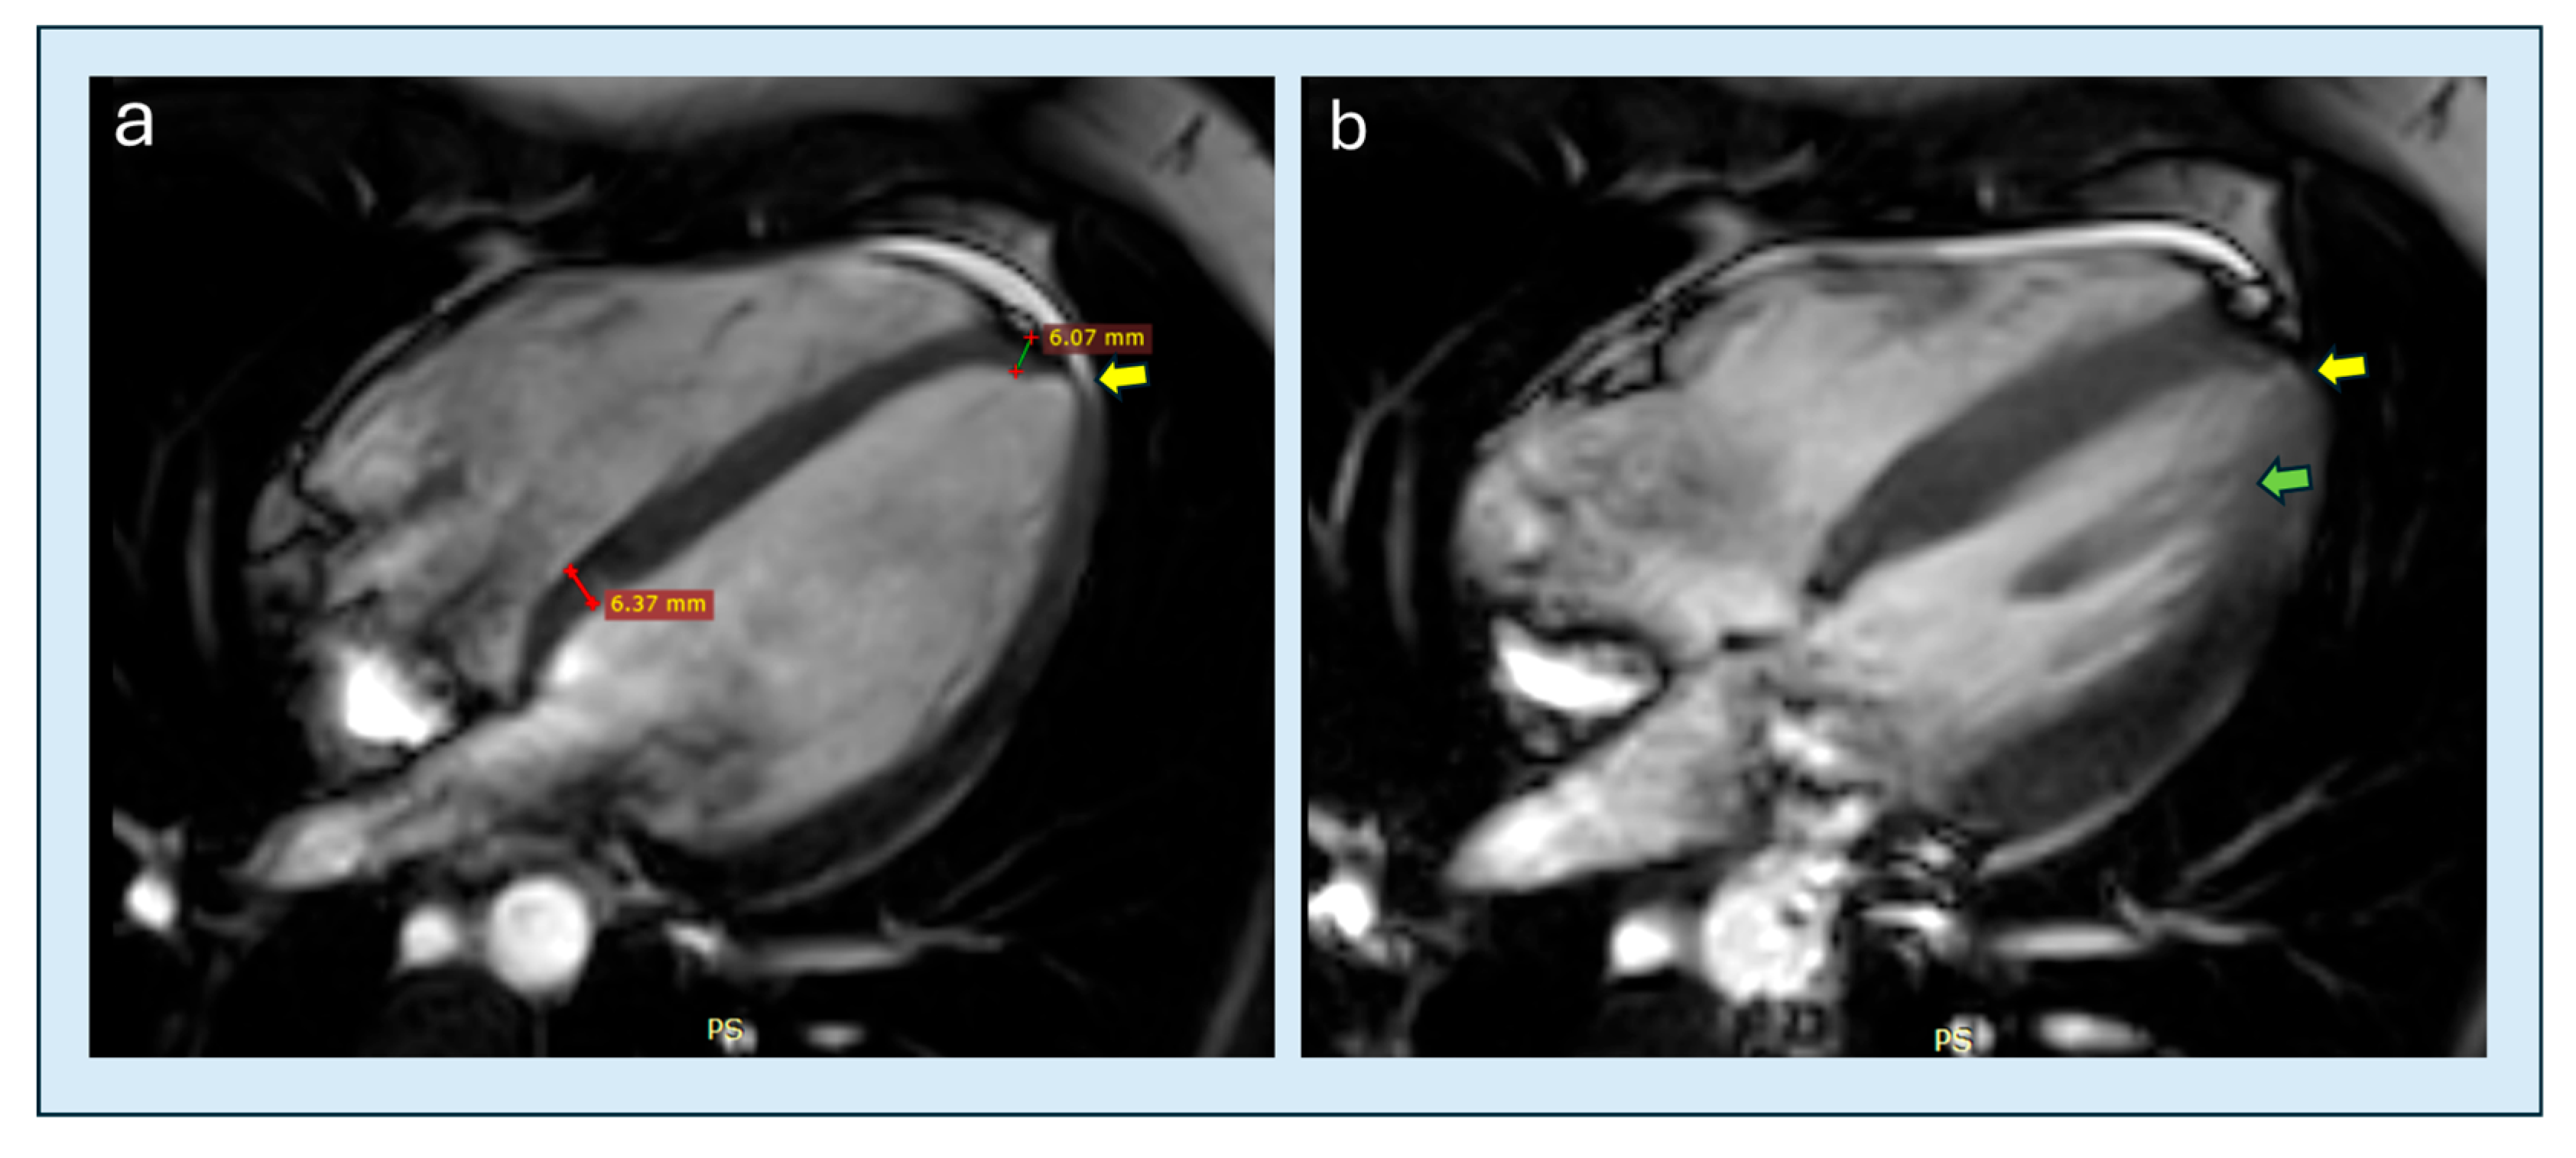

| Apical papillary displacement | CMRi | Apical beyond mid-LV | >150 HCM + ctrls | Supportive | Moderate | + | Filomena 2023 [76] |

| Apical cavity obliteration severity | TTE/CMRi | End-systolic closure | Echo/CMR cohorts | Prognostic | Moderate | +++ | Hamza 2025 [20] |

| Apical aneurysm detection | CMRi→TTE | Dyskinesis + scar | CMR aneurysm cohorts | Echo misses 43% | High | + | Hamza 2025 [20] |